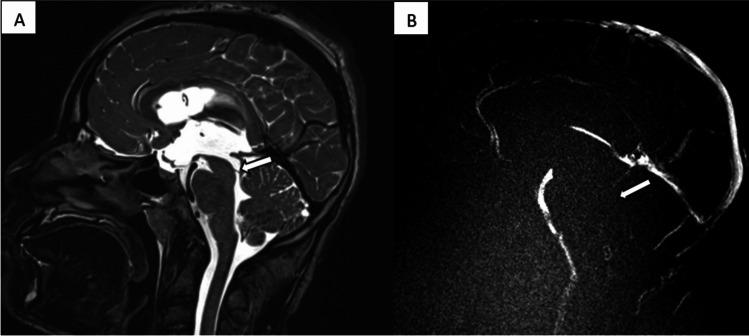

Herein, we describe a case of a child presenting with headaches and vomiting. Magnetic resonance imaging (MRI) revealed obstructive tri-ventricular hydrocephalus caused by an aqueductal web. Endoscopic third ventriculostomy (ETV) was successfully performed to restore cerebrospinal fluid (CSF) flow.

CONCLUSION

This case underscores the importance of phase-contrast and T2-weighted cinematic magnetic resonance imaging of cerebrospinal fluid flow for diagnosis of aqueductal webs. These modalities provide valuable insights into CSF dynamics and guidance of appropriate neurosurgical intervention.

在此,我们描述了一例以头痛和呕吐为表现的患儿。磁共振成像(MRI)显示由导水管狭窄引起的三脑室梗阻性脑积水。成功实施了内镜第三脑室造瘘术(ETV)以恢复脑脊液(CSF)流动。

结论

本病例强调了相位对比和 T2 加权电影磁共振成像在诊断导水管狭窄中的重要性。这些方法为 CSF 动力学提供了有价值的见解,并指导了适当的神经外科干预。